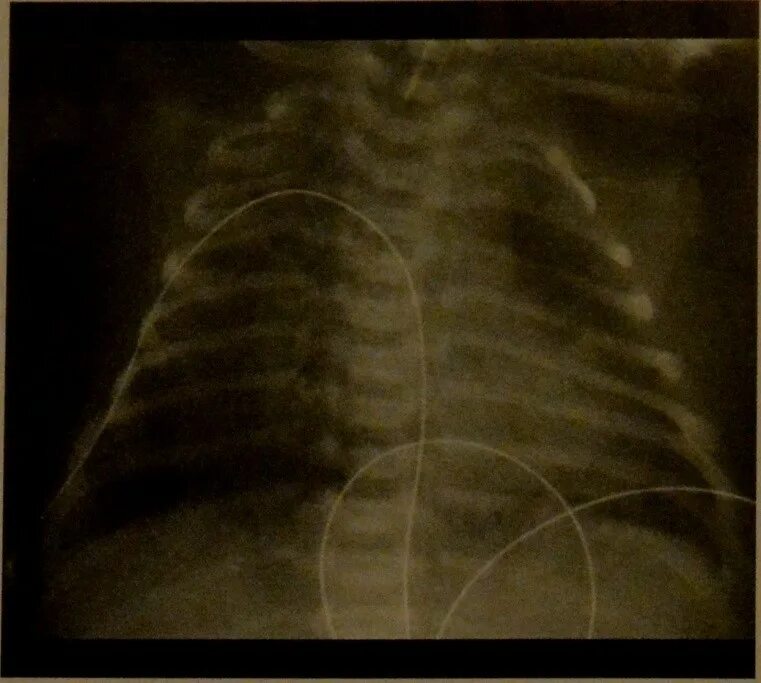

Синдром аспирации